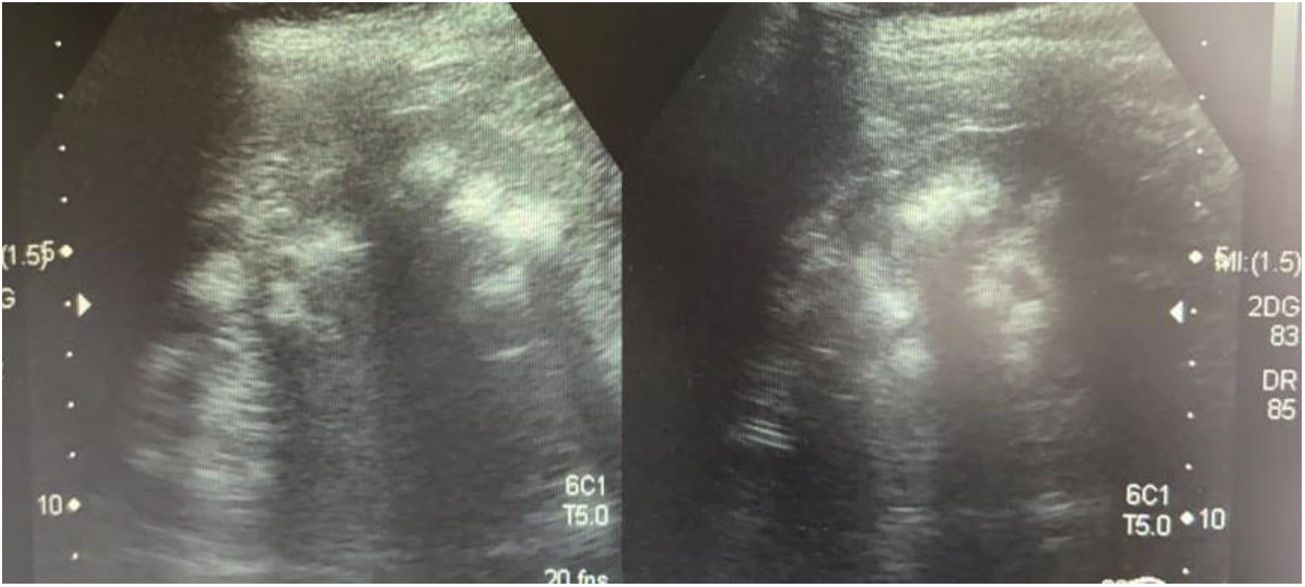

Caso 3La madre de los pacientes, de 29 años de edad, con antecedente de madre diabética y padre hipertenso en tratamiento. Hermano mayor con litiasis renal y episodios múltiples de parálisis flácida. Fue diagnosticada al realizar el abordaje diagnóstico de sus hijos. Con avidez por el agua desde la infancia. Su peso era 58kg, la talla 157cm y la presión arterial 100/60mmHg. Los niveles de creatinina eran 0,78mg/dl (CCr 122ml/min), el sodio 139mEq/l, el potasio 3,3mEq/l y la cloremia 113mEq/l. En la gasometría venosa se comprobó una acidosis metabólica (pH 7,17, HCO3− 14,1mEq/l) con hipocitraturia (14mg/24h) y proteinuria 382mg/24h (tabla 2). El pH urinario era 7 y el hiato aniónico (anión gap) urinario positivo (+36). En el ultrasonido renal se observó nefrocalcinosis medular grado II-III (fig. 3). Se comprobó la existencia de un cálculo en el tercio inferior ureteral derecho y otro de 1,5cm en la vejiga. Se realizó el estudio genético analizando los genes ATP6V0A4, ATP6V1B1 y SLC4A1. Se comprobó la presencia de una variante patogénica en heterocigosis en el exón 20 del gen SLC4A1, c.2710_*12, p. (Tyr904_Val911delins68) que se traduce en una deleción de 39 bases (27 del ultimo exón y 12 de la región 3’ UTR) que modifica la parte carboxi terminal de la proteína (deleción de los últimos 8 aminoácidos e inserción de una nueva secuencia de 68 aminoácidos). Esta variación no descrita en la literatura y no incluida en la base de datos, es considerada patógena, de acuerdo a la ACMG 2015, clase 5 (American College of Medical Genetics and Genomics); los criterios usados para clasificarla en clase 5 son: PVS1, PM2, PM1, PM4. Esta variación no está presente en la base de datos de población general gnomAD (criterio PM2)

Ecografía realizada a la madre de los pacientes. Riñones con ecogenicidad heterogénea a expensas de un aumento de la ecogenicidad de las pirámides renales compatible con nefrocalcinosis medular bilateral grado II-III. La relación córtico medular es poco nítida, con datos de nefropatía crónica difusa.